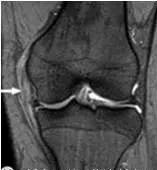

4、桶柄状撕裂

为纵形撕裂伴碎片向内侧移位,这种移位的片段类似于桶的柄,该型撕裂几乎累及半月板的所有部位,常易漏诊,在 MRI 上可以有多种表现,主要为半月板的宽度减小,在通过半月板体部的冠状面上未见到与对侧半月板共同构成的蝶形表现,同时可见到内移的半月板碎片位于髁间窝或交叉韧带旁,可形成双前、后交叉韧带征,这一征象在诊断半月板桶柄状撕裂中有重要意义;